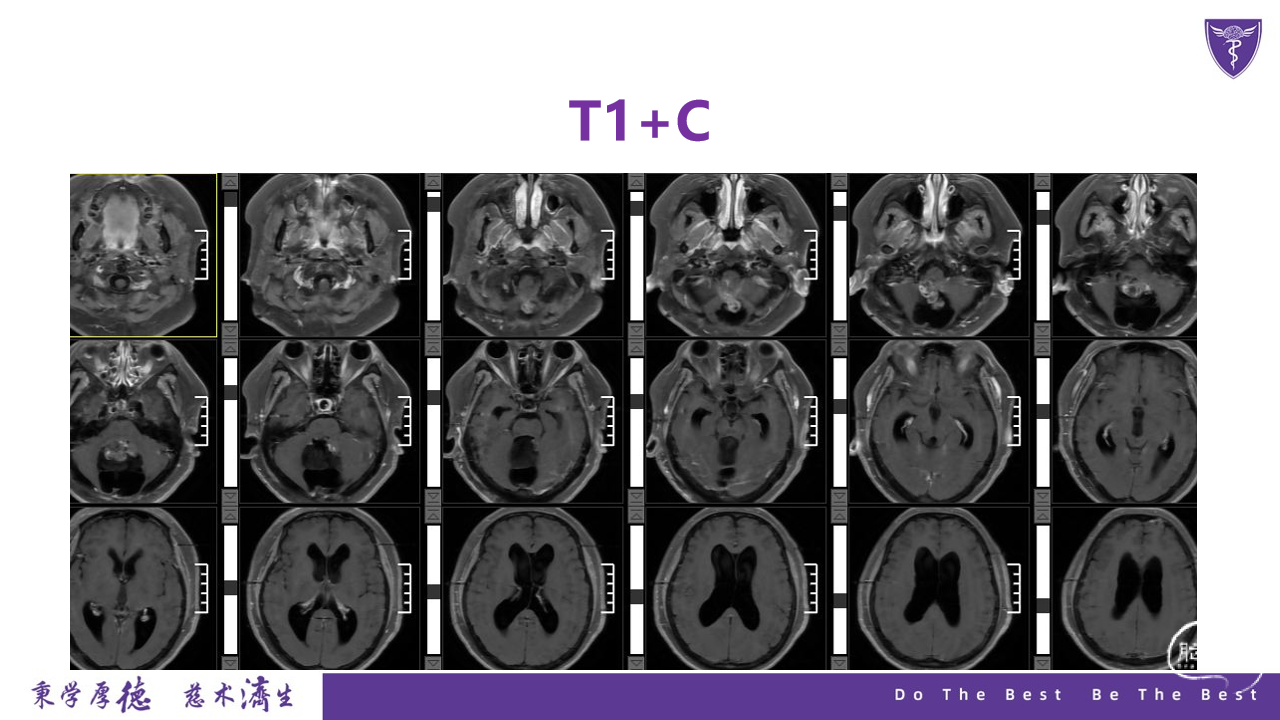

王杰教授团队:四脑室复发室管膜瘤切除术